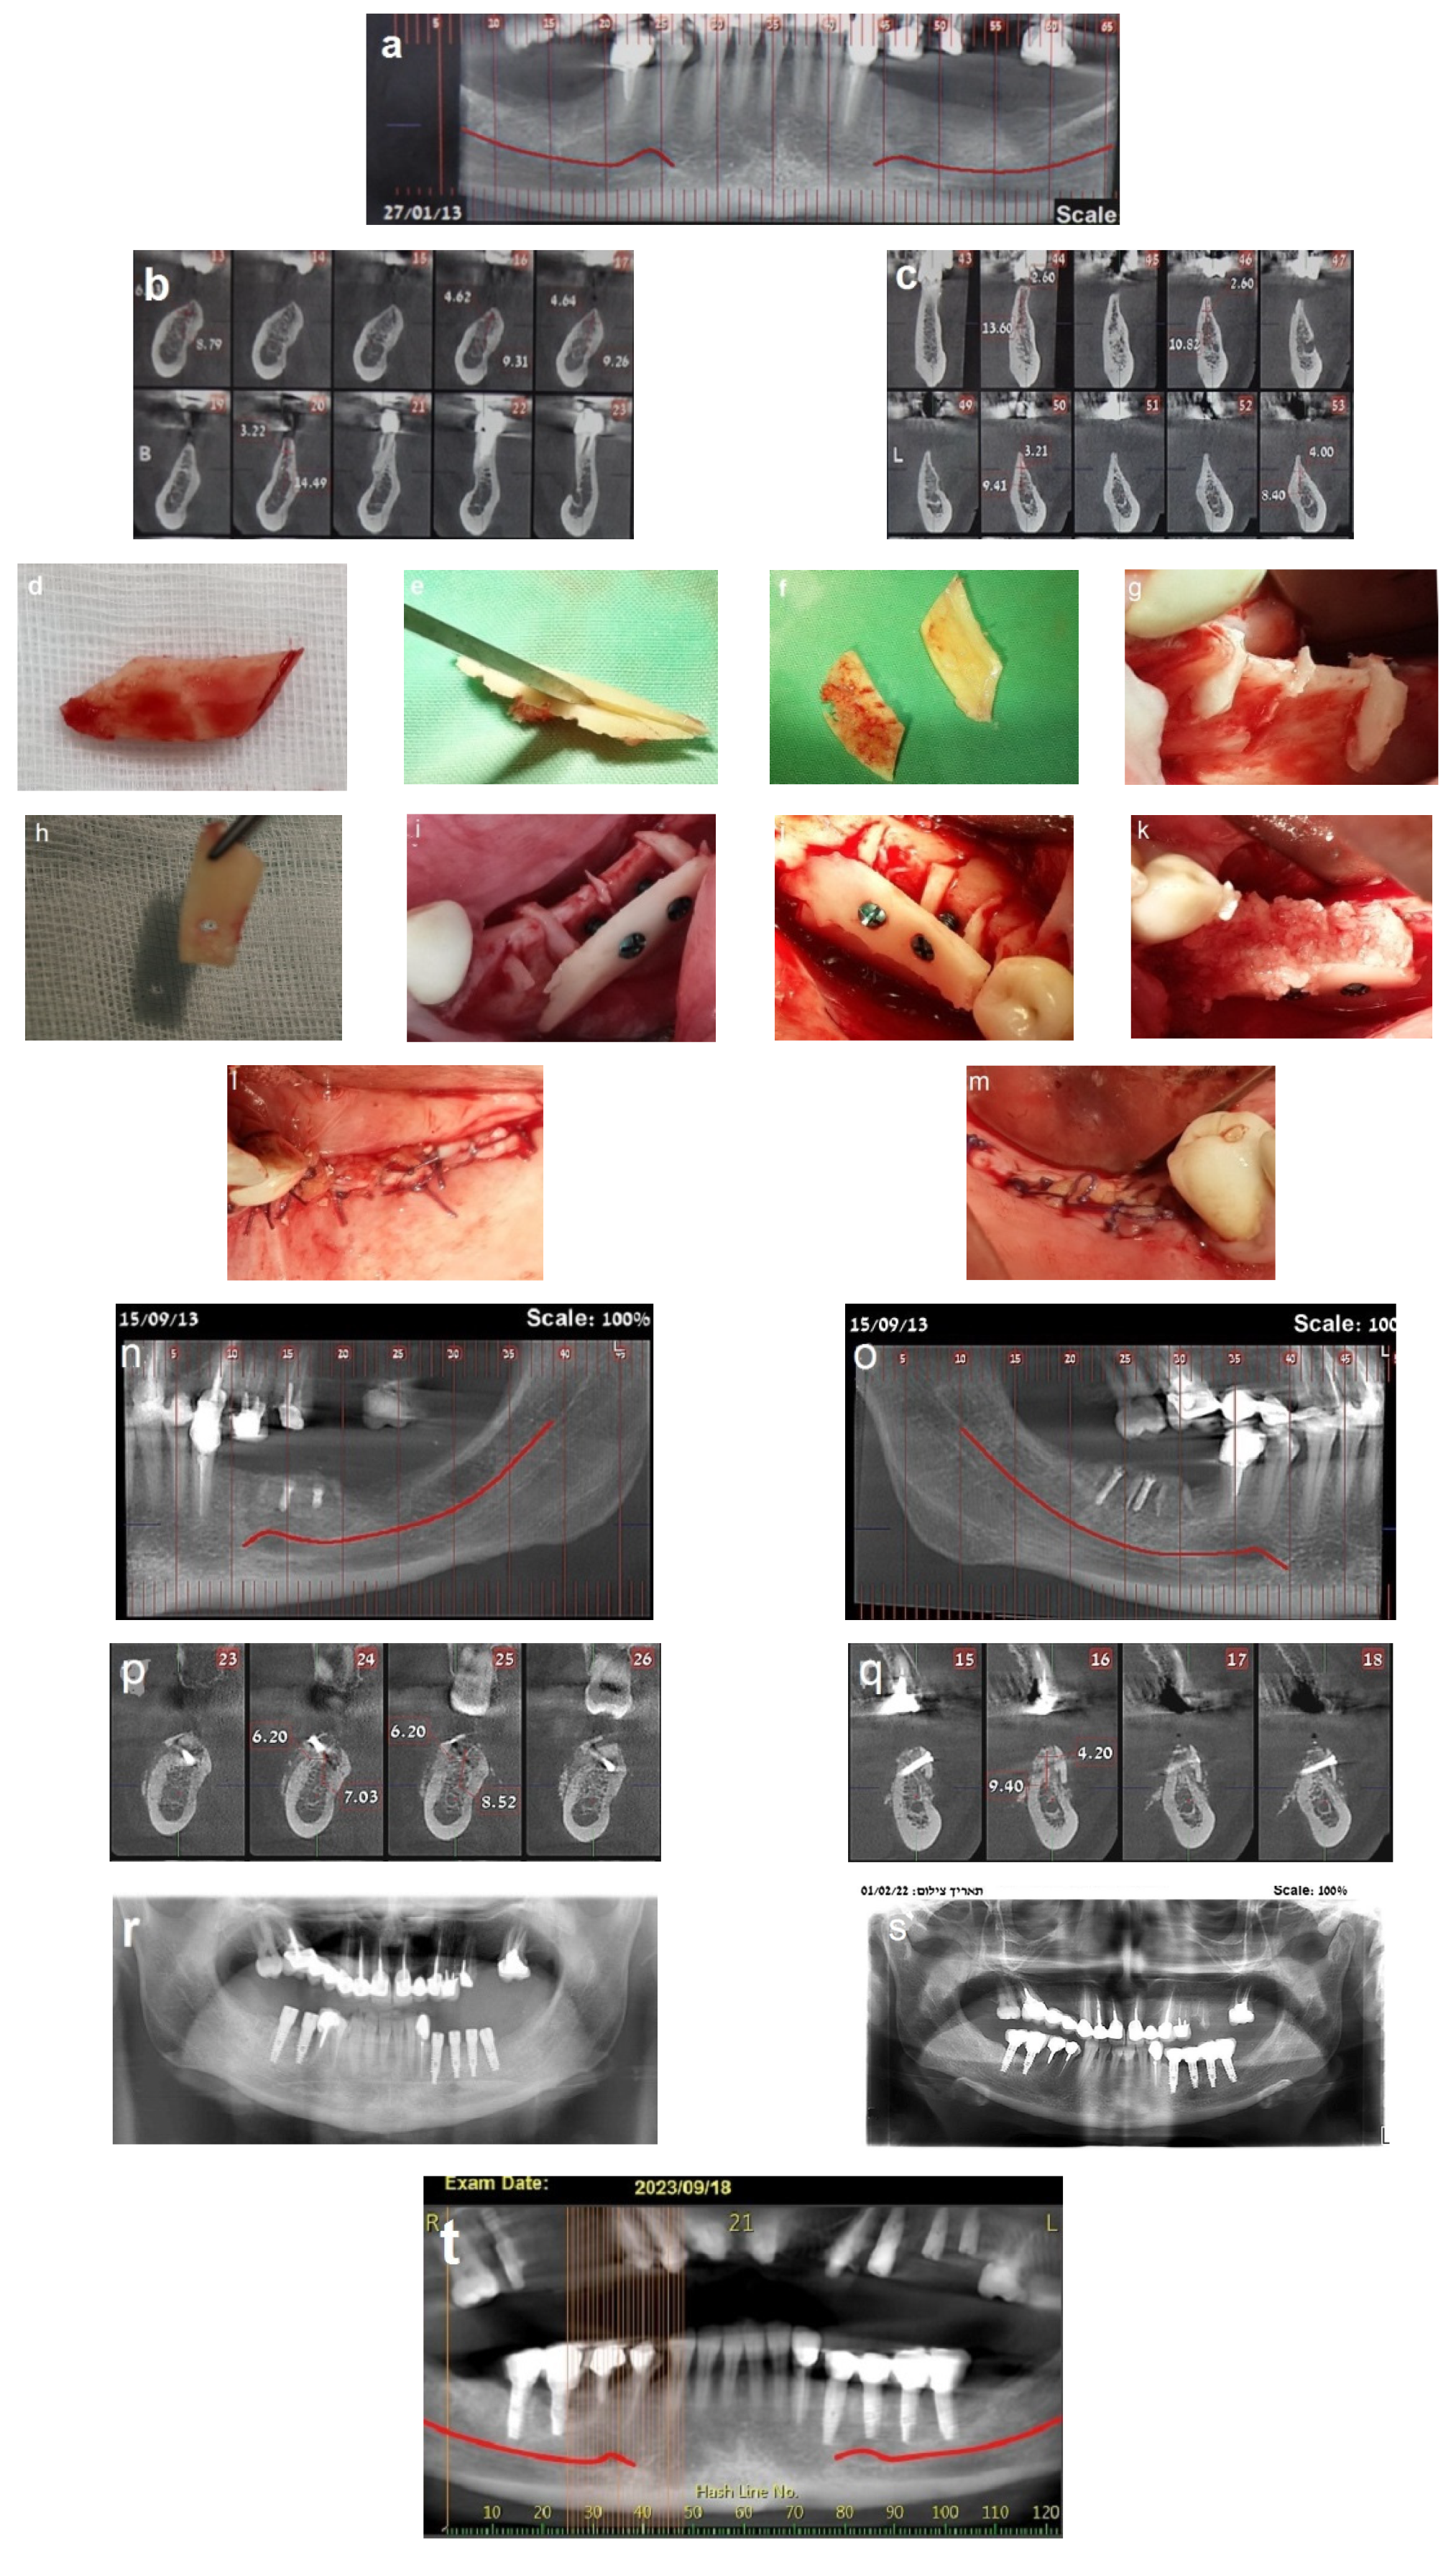

Follow-up was scheduled three times every two weeks, then monthly. Partial exposure of the graft occurred at four weeks on the right side but was successfully managed without compromising the augmentation outcome. A CBCT scan was obtained after four months to assess the bone gain (Figure 4a–c). Dental implants were placed 4 months after the procedure (Figure 4d–i). A fixed prosthesis was delivered four months after the implant placement. This case was followed for 10 years (Figure 5).

Figure 4.

Reentry at 4 months. (a–c) CBCT post-op demonstrating significant horizontal bone gain. (d) Left-side view, showing excellent integration of the bone blocks and the width of the new bone demonstrated by the length of the removed fixation screws (e). (f,g) Placement of three implants on the left side. (h) New bone volume on the right side. (i) Placement of three implants on the right side.

Figure 5.

Follow-up. (a,b) Ten-year follow-up post-loading, showing the implant at the recipient site with no marginal bone loss.

A 36-year-old woman was referred for bone augmentation and dental implant placement in the atrophic posterior mandibular ridges. The examination revealed partial edentulism of the mandible, with missing posterior teeth on both the right and left sides (Figure 6a). Computed tomography confirmed a significant horizontal bone deficit in the posterior mandibular regions bilaterally (Figure 6b,c). A two-stage treatment approach was planned. In the first stage, the honeycomb bone (HCT) technique was employed to augment the right and left posterior mandibular regions.

Figure 6.

(a) Bilateral posterior mandibular edentulism. (b,c) Computed tomography showing severe horizontal atrophy with knife-edge residual ridges. (d) The bone block harvested from the retromolar donor site. (e,f) The harvested bone block and its subsequent splitting, resulting in thin bone blocks and cortical wedges. (g) The bone augmentation procedure: grooves were created using high-speed at the recipient site, followed by the insertion and tapping of the cortical bone wedges into the grooves. (h,i) A thin bone plate is positioned over the bone wedges and secured with screws, creating bone compartments resembling a honeycomb. (j) Right side. (k) The bone compartments are filled with allogenic particulate bone graft to achieve the desired graft volume on the right side. (l,m) Double-layer, tension-free closure of the recipient sites performed using BFFGs. (n–q) CBCT scan, four months postoperatively show significant bilateral horizontal bone gain. (r) Two implants were placed on the right side and four implants on the left side. (s) Panoramic view at 8-year follow-up. (t–v) CBCT scans taken 10 years after implant placement reveal stable augmented bone levels. (w) Eleven-year follow-up periapical x-ray of the left side, demonstrating no significant marginal bone loss. (x) 3 mm of marginal bone loss observed at the mesial implant. The yellow arrows show the cortical wedges that remain visible at the recipient sites.

In May 2013, a cortical bone block was harvested from the right retromolar area (Figure 6d). The harvested block was then split, yielding two thin bone blocks and multiple bone wedges (Figure 6e,f). The recipient sites were prepared by creating grooves, into which the bone wedges were inserted in a stable position bilaterally (Figure 6g). Two thin bone blocks were then secured over the bone wedges using screws. This configuration resulted in multiple bone compartments resembling a honeycomb structure (Figure 6h–j). After trimming any sharp edges, the compartments were filled with particulate allograft bone substitute, achieving the desired final bone volume (Figure 6k). The augmented sites were then covered with a resorbable membrane and a free buccal fat pad graft (BFFG) before being closed in a tension-free manner (Figure 6l,m). The healing process was uneventful throughout the follow-up period. A CBCT scan performed four months postoperatively, in September 2013, confirmed significant horizontal bone gain of 4–6 mm (Figure 6n–q). Upon reentry under local anesthesia, the newly formed bone volume was evident, with the bone wedges fully integrated into the regenerated bone mass. Six dental implants were successfully placed (Figure 6r). After three months, all the implants had achieved full osseointegration, allowing for final prosthetic rehabilitation. This case has been followed for 11 years. A panorex obtained at 8 years showed implants without marginal bone loss (Figure 6s), and a CBCT scan obtained in September 2023 demonstrated stable bone volume 10 years post-surgery, with no resorption of the augmented bone blocks (Figure 6t–v). Periapical radiographs taken in July 2024 further confirmed the long-term stability of the outcomes and implant survival. At this time, the first implant on the right side showed a 3mm marginal bone loss, possibly due to food impaction from a decayed adjacent premolar. The remaining five implants exhibited no signs of marginal bone loss. The cortical wedges remained visible at the recipient sites in both figures (Figure 6w,x).